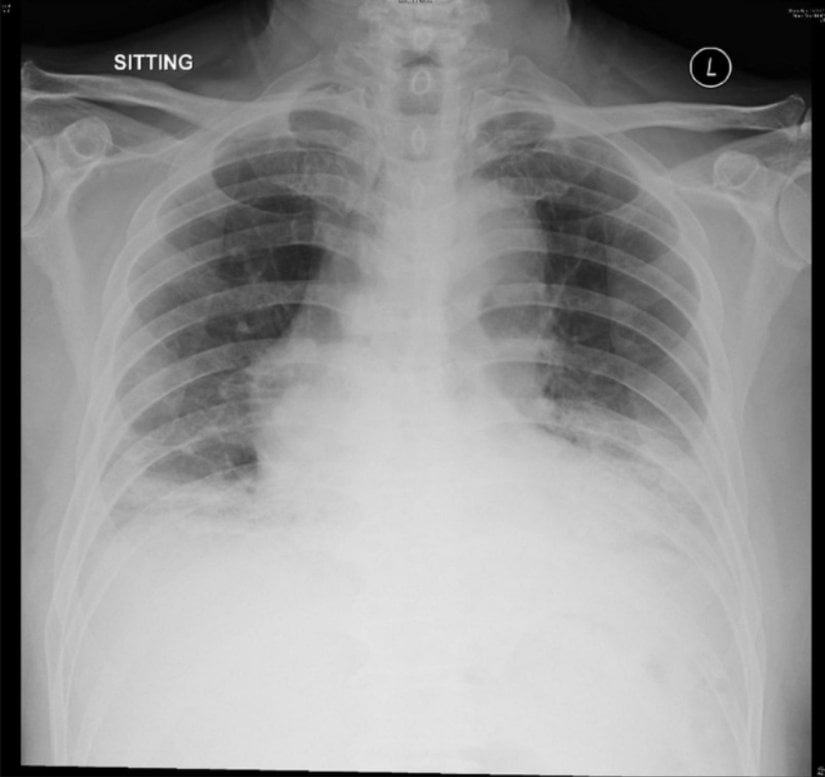

- Pnömoni.

Soğuk algınlığına sebep olan koronavirüslerin geri kalanı gibi bu virüs de bebekler, yaşlılar, kanser hastaları ve HIV+/AIDS hastaları için risk teşkil etmektedir. Çoğunlukla üst solunum yolu enfeksiyonuna sebep olan virüsün risk grubundaki hastalarda viral pnömoni dahil daha ciddi alt solunum yolu sendromlarına yol açması muhtemeldir. Ensefalite (beyin-omurilik iltihabına) çevirme olasılığı sebebiyle halihazırda sinir sistemi bozukluğu olan bireyler için bu olasılık da diğer nezle koronavirüslerinde olmayan bir risk teşkil etmektedir.

Ciddi vakalarda ise görüş birliğine varılmış bir OC43 tedavisi olmadığı için bağışıklık sistemine destek olma ve hastanın rahatlatılması amaçlanır. Çeşitli antiviral kokteylleri denenebilir ancak bunların prognozu iyileştirdiği yönünde bir bilimsel fikir birliği yoktur. İntravenöz immün globülin veya pasif bağışıklanma yöntemi, klinik olarak %100 etkili olmasa da denenen yöntemler arasındadır. Ağır vakalarda akut akciğer hasarı meydana geldiğinden mekanik ventilasyona başlanabilir.